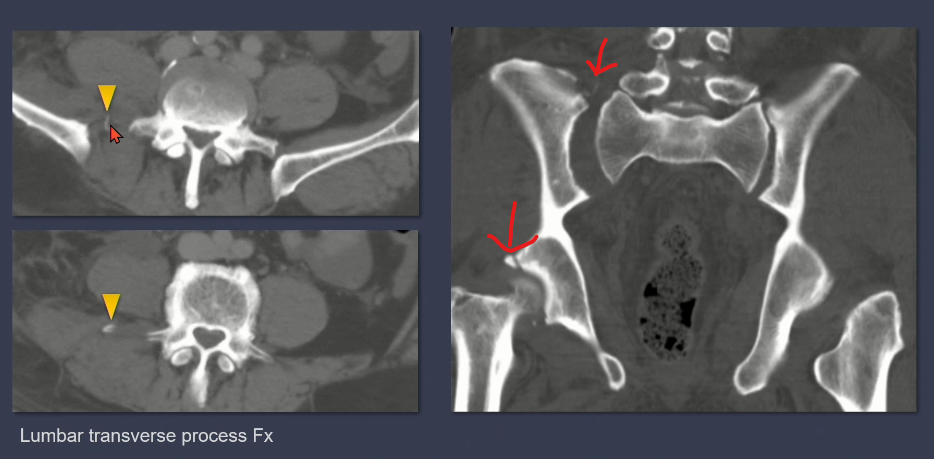

3. LC type